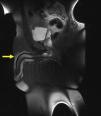

MRI findingsSagittal MRI sequences of the penis revealed a thrombosis in the superficial vein of the penis under the skin on the dorsal penis (Figs. 2 and 3). Doppler USG of the penis supported the diagnosis with the lack of flow in the superficial vein of the penis due to thrombosis. The Doppler USG also showed low velocity and highly resistant flow in the cavernous arteries.

The diagnosis of PMD using MRI is a controversial subject. The improved image quality in MRI and the use of godalinum during the procedure as an angiographic agent allowed the evaluation of early arterial and late venous phases. However, this procedure can only be recommended for cases in which a diagnosis or differential diagnosis could not be established. Systemic fibrosis is the most important factor limiting the use of MRI-angiography. There is only one case report in the literature that was diagnosed using MRI-angiography. This procedure was reported to be helpful in the diagnostic process due to the coexistence of various diseases and symptoms.14 The currently reported case is valuable for the demonstration of the possibility of diagnosing the condition without using godalinum to avoid the risk of systemic fibrosis.